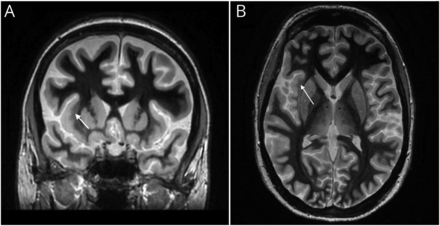

鉴于脑电图焦快速活动,有高怀疑焦皮质发育不良(FCD)。因为之前MRI 3 T发作协议研究正常和7 T MRI中可用的状态,3 T MRI与快速灰质收购T1反转恢复(FGATIR)序列。MRI与FGATIR序列显示焦点在正确的岛叶皮质与皮质增厚模糊的灰白色物质界面,符合FCD (图2)。病人从lacosamide clobazam因为关心公关间隔延长,这可能会延迟复苏。她有一个起搏器安置,目前与即将到来的stereo-EEG评价癫痫手术。